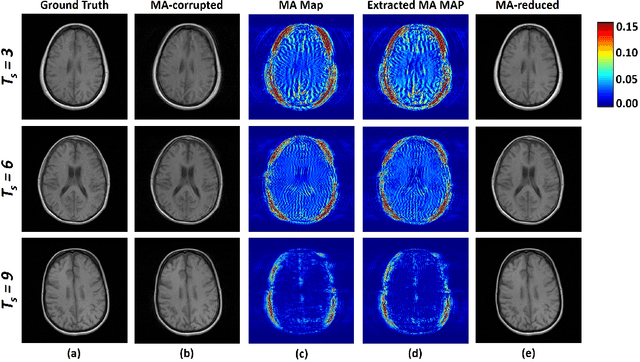

Abstract:Motion artifact reduction is one of the most concerned problems in magnetic resonance imaging. As a promising solution, deep learning-based methods have been widely investigated for artifact reduction tasks in MRI. As a retrospective processing method, neural network does not cost additional acquisition time or require new acquisition equipment, and seems to work better than traditional artifact reduction methods. In the previous study, training such models require the paired motion-corrupted and motion-free MR images. However, it is extremely tough or even impossible to obtain these images in reality because patients have difficulty in maintaining the same state during two image acquisition, which makes the training in a supervised manner impractical. In this work, we proposed a new unsupervised abnomality extraction network (UNAEN) to alleviate this problem. Our network realizes the transition from artifact domain to motion-free domain by processing the abnormal information introduced by artifact in unpaired MR images. Different from directly generating artifact reduction results from motion-corrupted MR images, we adopted the strategy of abnomality extraction to indirectly correct the impact of artifact in MR images by learning the deep features. Experimental results show that our method is superior to state-of-the-art networks and can potentially be applied in real clinical settings.